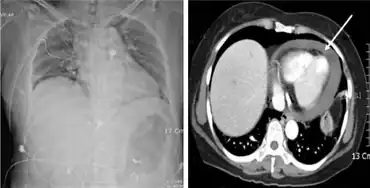

Hemopericardium can be diagnosed with a chest X-ray or a chest ultrasound, and is most commonly treated with pericardiocentesis.[6] While hemopericardium itself is not deadly, it can lead to cardiac tamponade, a condition that is fatal if left untreated.[6]

Hemopericardium can be diagnosed using echocardiography, a cardiac ultrasound.[6] Chest X-rays are also often taken when hemopericardium is suspected and would reveal an enlarged heart.[6]